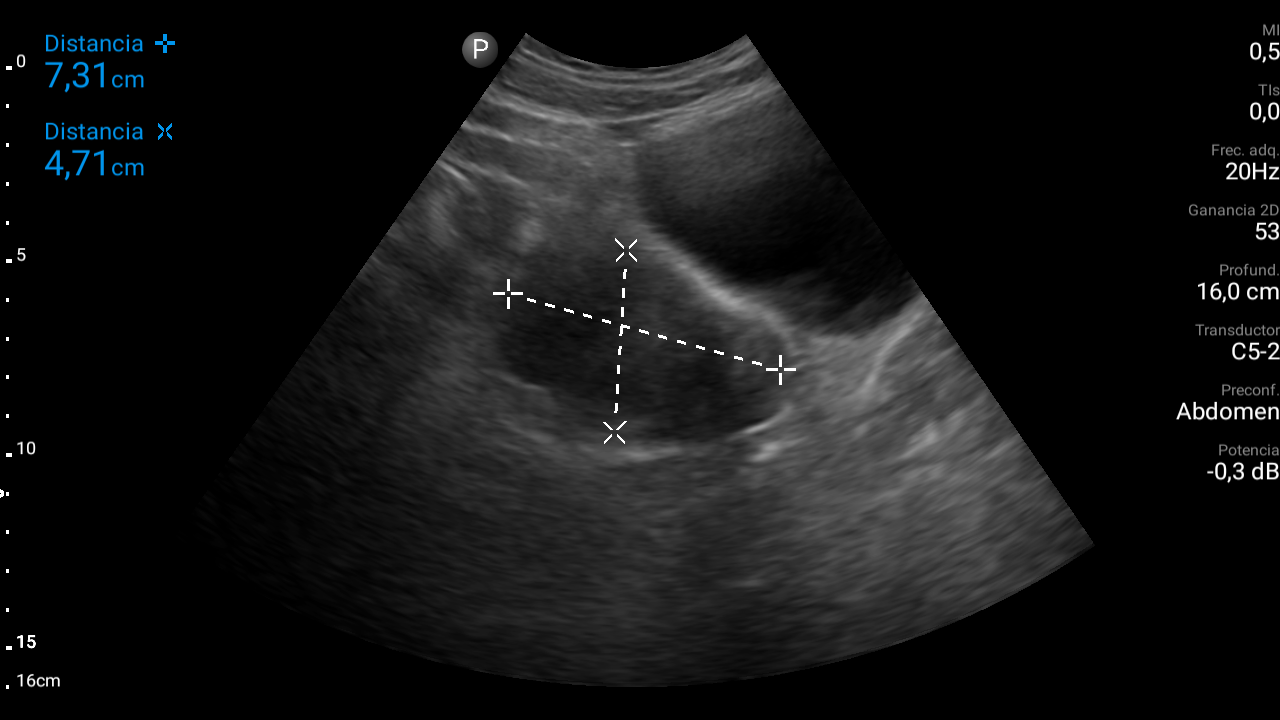

Ecografía abdominal: se observa masa hipoecoica dependiente de útero por lo que se remite de forma preferente a ginecología.

Diagnóstico: mioma uterino.El diagnóstico diferencial habría que realizarlo entre adenomitosis (ausencia de cápsula que separa la formación del tejido miometrial normal), sarcoma, leiomiosarcoma (tumor maligno), salpingitis, endometriosis, embarazo ectópico, torsión ovárica, rotura de ovario, patología urológica (cólico nefrítico…) o patología digestiva (enfermedad inflamatoria intestinal, pseudoobstrucción intestinal…).